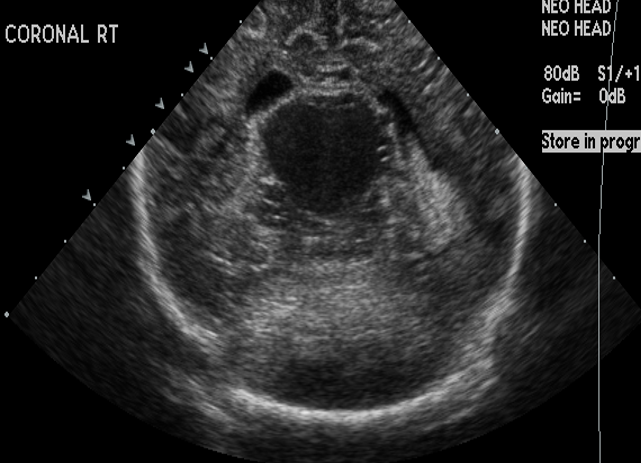

CSF spaces/ventricular system

There is prominence of the ventricular system. [Yes/No]

There is an asymmetry of the ventricular system. [Yes/No]

The lateral ventricle/s are dilated. [Yes/No]

The third ventricle is dilated. [Yes/No]